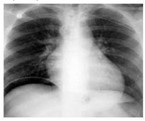

* TUBERCULOSE